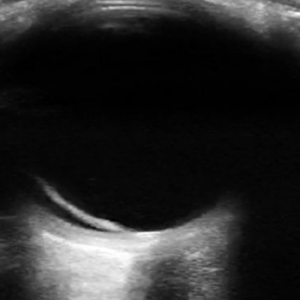

Figure 1: The optic nerve appears posteriorly as a hypoechoic structure and is measured 3 mm posterior to the globe.